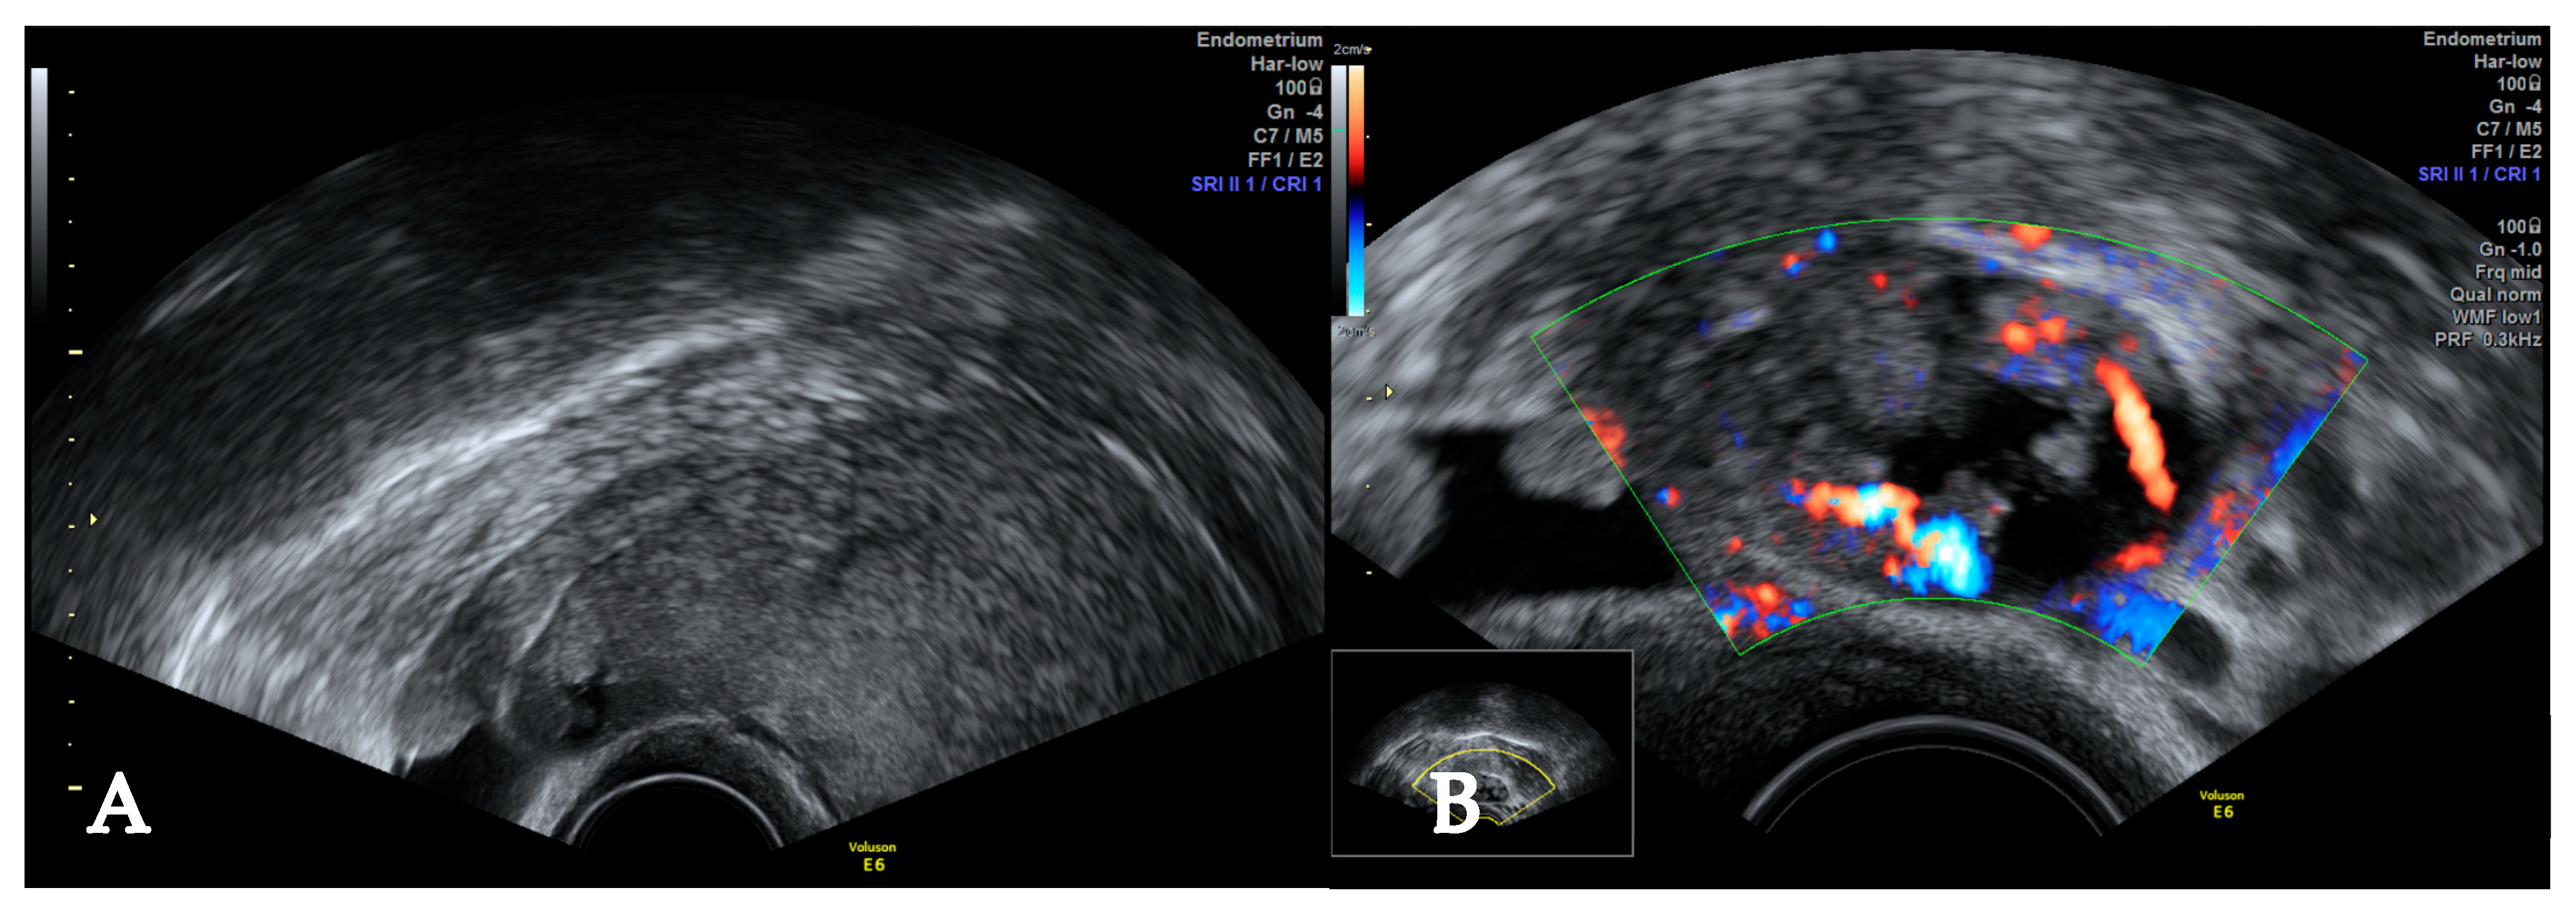

2. Case

4.1. Diagnostic Challenges